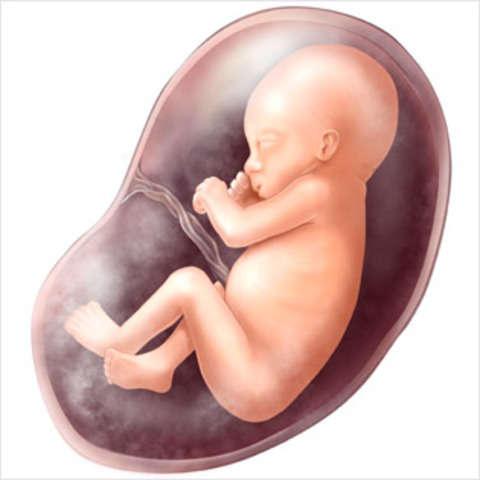

• week 37 of the fetal development

week 37 of the fetal development

Fetus gainsabout a pound a week., Orgains grow stronger. Finger nails extended past the fingertips. Head hair is coarse and thicker.